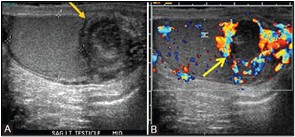

Genel olarak testis tümörü hastalar tarafından fark edilir ve doktora başvururlar. Doktorlar hastayı muayene ettikten sonra ultrasonografi yapılır (Şekil 2) ve bu şekilde testis tümörü tanısı netleşir. Bunun yanında hastadan yukarıda belirtilen tümör belirteçlerinin (AFP ve hCG) kan düzeyleri istenir. AFP düzeyinin yüksek olması hastanın kanserinde her zaman bir non-seminomatöz kısmın olduğunu gösterir. Bunun yanında üçüncü bir tümör belirteci olan ve genel olarak yaygın hastalığı gösteren serum laktat dehidrogenaz (LDH) düzeyine de bakılır. Tüm bunlarla tanı netleştirildikten sonra hasta cerrahi tedaviye yani testisinin alınmasına hazırlanır.

Şekil 2: Testis tümörünün ultrasonografideki görüntüsü. B: Doppler modunda kanlanması artmış tümör görülmekte.